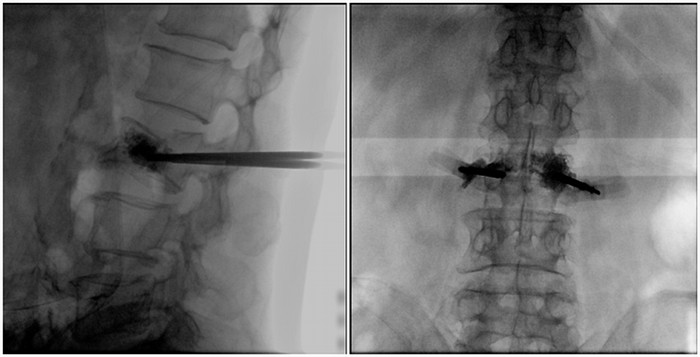

術(shù)中切口5毫米,在大平板C臂機(jī)的透視指引下,確定了進(jìn)針的方向及進(jìn)針的深度。經(jīng)椎弓根向椎體置管,建立通道,插入骨擴(kuò)張器(球囊)。球囊擴(kuò)張恢復(fù)椎體高度,并在椎體內(nèi)形成空腔,確定骨水泥的注入劑量,并注入骨水泥觀察其擴(kuò)散情況。

大平板C臂機(jī)臨床圖像

市面上主流的小C大多采用21CM×21CM的平板或者影像增強(qiáng)器,成像范圍較小,一般可成像3.5節(jié)腰椎,確定傷椎可能需要進(jìn)行多次拍攝。普愛(ài)醫(yī)療大平板C臂機(jī)采用30CM×30CM的平板探測(cè)器,一般可一次性成像5節(jié)腰椎,呈現(xiàn)更廣闊的視野。使醫(yī)生一次性全面地觀察到傷椎及周?chē)刁w情況,使得手術(shù)效率更高、更準(zhǔn)確。如果您想采購(gòu),或了解這款大平板C臂機(jī)技術(shù)參數(shù),歡迎咨詢400-025-6366。